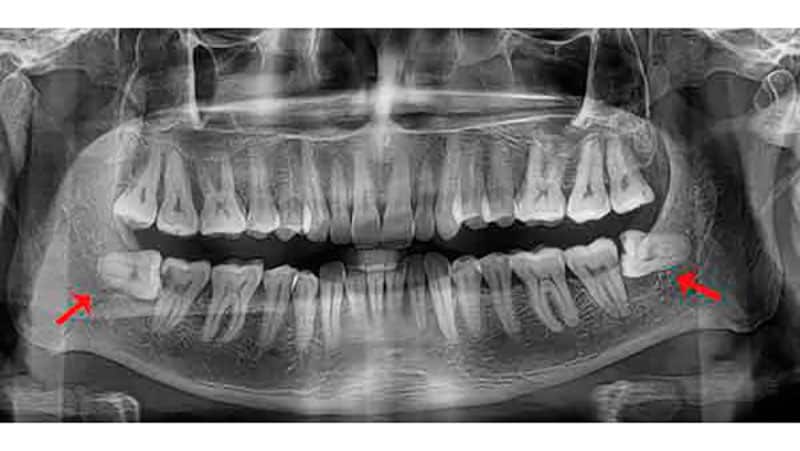

Зубы мудрости начинают формироваться у плода в утробе матери, и последними появляются в возрасте 17-25 лет. Удаление зуба мудрости на нижней челюсти может быть очень болезненным и становится трудным испытанием для многих людей.

Зубы мудрости получили свое название из-за возраста, в котором они появляются. К этому времени остальные 28 зубов уже находятся во рту. Поэтому зубам мудрости часто не хватает места и они остаются «застрявшими». Это явление называется ретенцией в стоматологии. Часто хирургам приходится удалять зуб мудрости на нижней челюсти, особенно у людей старше 30 лет, и это может иметь серьезные последствия.

- Зубы мудрости могут иметь разное количество корней — от одного до четырех. Определить точное количество корней часто бывает сложно.